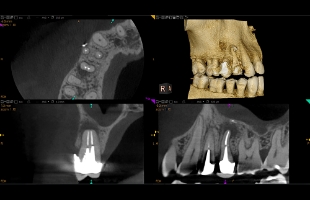

歯科用CTを使った

正確な診断

プラザデンタル クリニックでは、より正確な診査診断をおこなうために、歯科用CT(TROPHYPAN SUPREME 3D)を導入しております。

歯科用CTとは、CT撮影装置とコンピューター処理により、3次元的に画像処理を行うことで、骨・血管・神経の状態を正確かつ高精度に診断することができる装置のことを言います。

従来のレントゲンでは把握することの難しかった骨密度の診査や、顎の骨の立体的な形態、歯と神経の位置関係を確認することも可能となります。

当院導入の歯科用CT(TROPHYPAN SUPREME 3D)の特徴

- 撮影モードごとに、患者様の体型・線量・顎骨形状など全ての位置づけ情報を記憶

- 側方だけでなく水平断面の実像でダイレクトに撮影領域を決定

- 面積線量を軽減しながら画質を向上

- MAR(メタルアーチファクト軽減機能)で優れた画像処理を実現

- フェイススキャンで顔貌の立体画像と3D画像をマッチングが可能